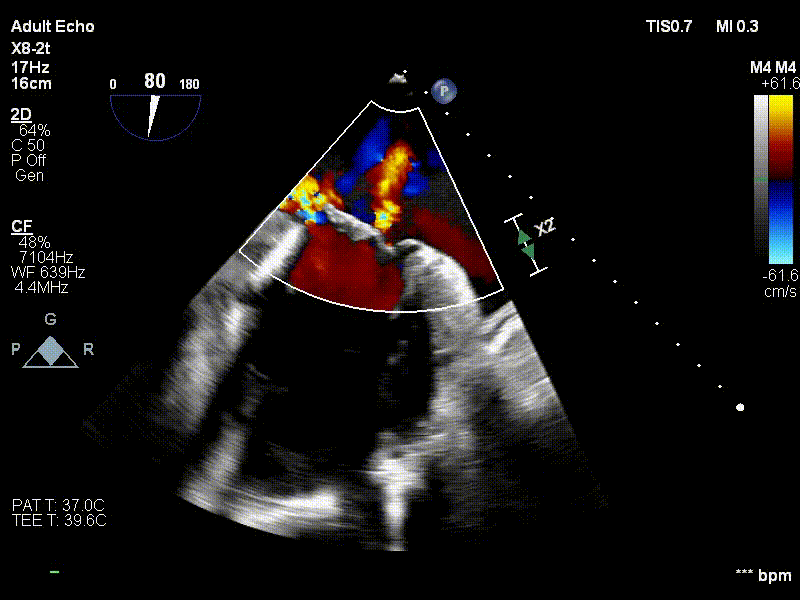

术前心超二尖瓣重度反流

术中超声瓣膜定位

术中超声瓣膜释放

术后复查心超二尖瓣反流消失